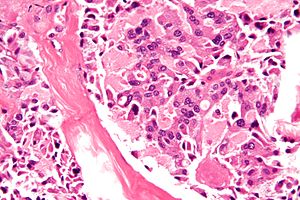

Під терміном «синдром множинних ендокринних пухлин (або неоплазій)» (МЕН) об’єднують захворювання, при яких виявляються пухлини нейроендокринного походження і/або гіперплазії (дифузні, вузликові) в двох або більше ендокринних органах.

Аутоімунні поліендокринні синдроми – група захворювань, які об’єднані між собою спільними патогенетичними механізмами і проявляються множинною ендокринною недостатністю.